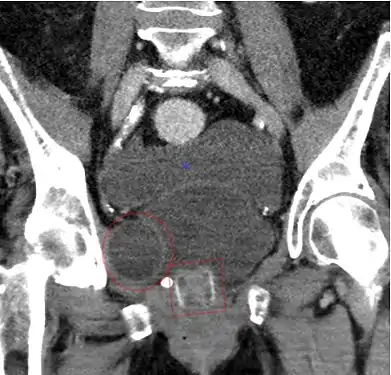

Transobturator tape

The transobturator tape (TOT or Monarc) sling procedure aims to eliminate stress urinary incontinence by providing support under the urethra. The minimally-invasive procedure eliminates retropubic needle passage and involves inserting a mesh tape under the urethra through three small incisions in the groin area.[19]